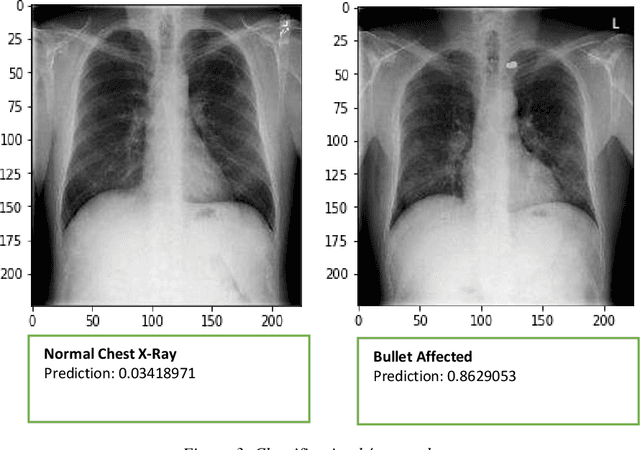

Abstract:The potential of deep learning, especially in medical imaging, initiated astonishing results and improved the methodologies after every passing day. Deep learning in radiology provides the opportunity to classify, detect and segment different diseases automatically. In the proposed study, we worked on a non-trivial aspect of medical imaging where we classified and localized the X-Rays affected by bullets. We tested Images on different classification and localization models to get considerable accuracy. The replicated data set used in the study was replicated on different images of chest X-Rays. The proposed model worked not only on chest radiographs but other body organs X-rays like leg, abdomen, head, even the training dataset based on chest radiographs. Custom models have been used for classification and localization purposes after tuning parameters. Finally, the results of our findings manifested using different frameworks. This might assist the research enlightening towards this field. To the best of our knowledge, this is the first study on the detection and classification of radiographs affected by bullets using deep learning.